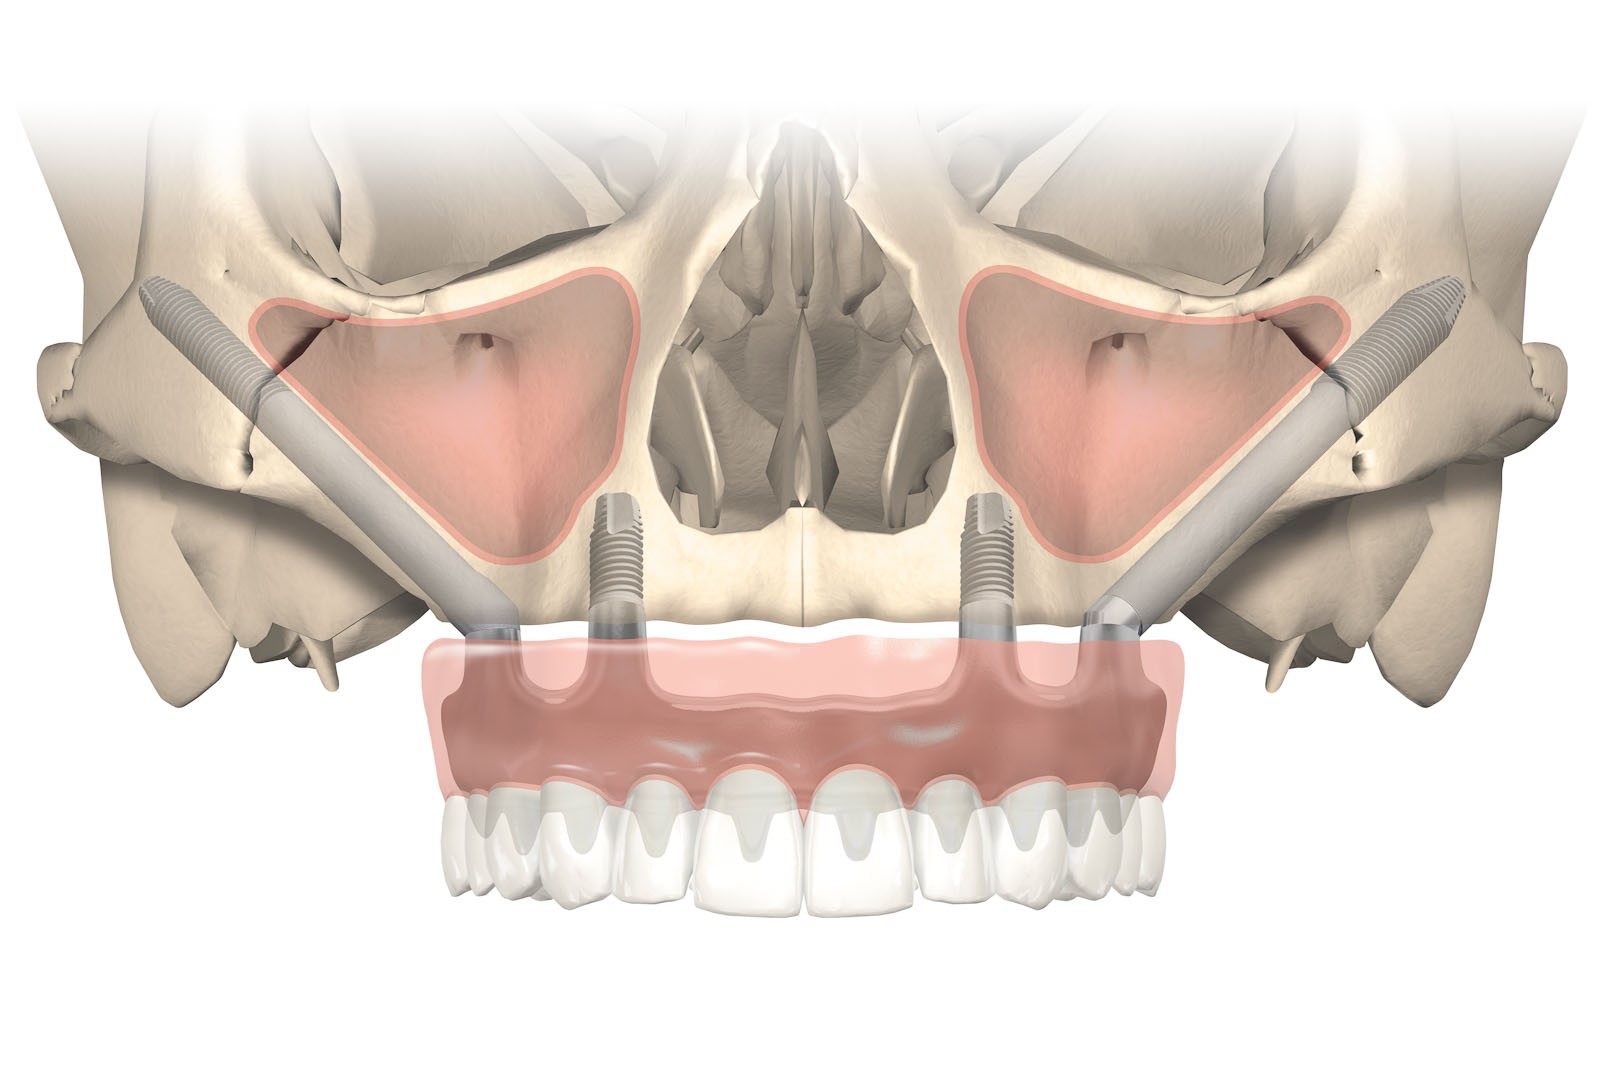

- Zastosowanie implantów Zygoma w bocznych odcinkach szczęk przy rozległych zanikach szczęk

- Zastosowanie implantów skrzydłowych